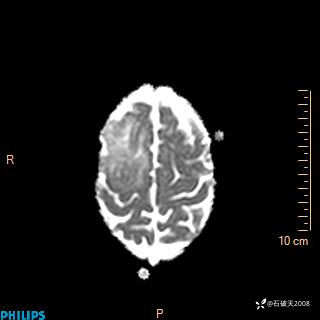

2024.2.21MR

DWI